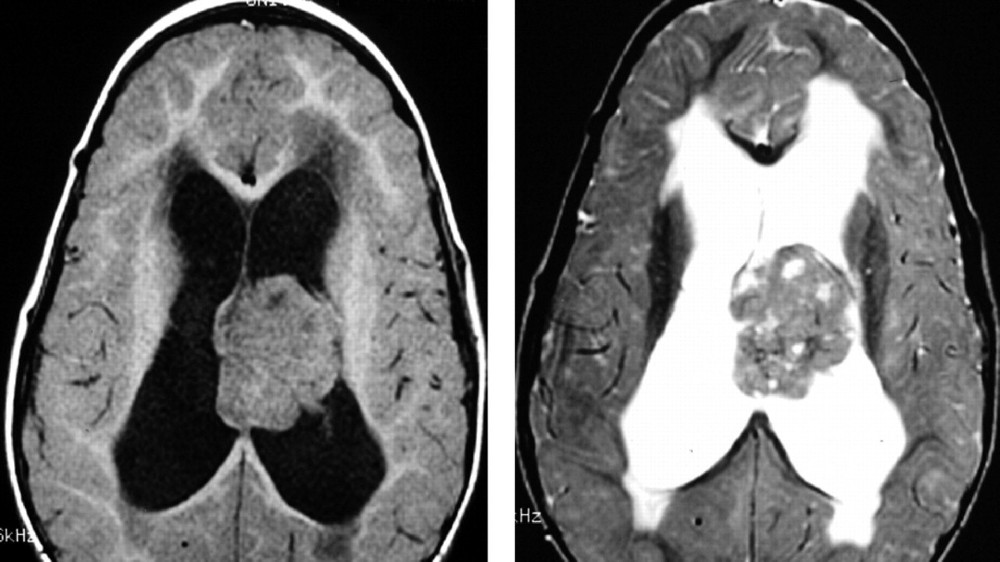

鑑於 ATRT 的侵襲性及新陳代謝的依賴性,早期發現變得至關重要。我們強烈建議定期進行基因篩檢和先進的影像診斷技術,尤其是對於高風險族群,以便及時介入治療。